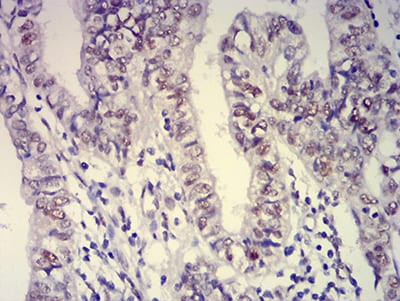

Immunohistochemical analysis of paraffin-embedded human endometrial cancer tissues using ATXN1 mouse mAb with DAB staining.